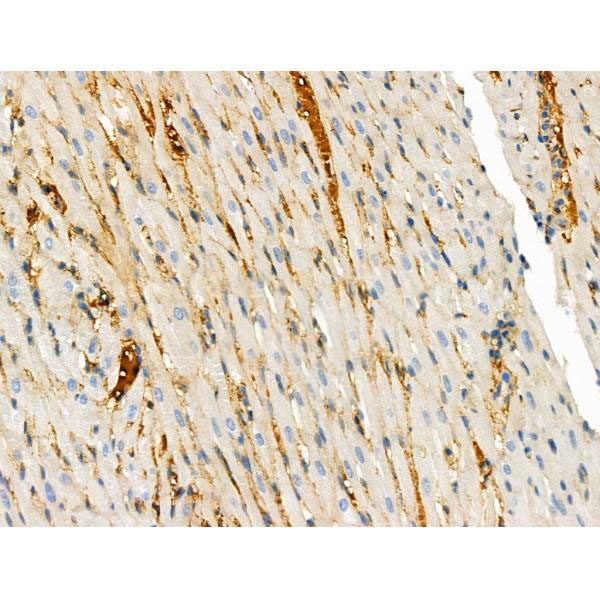

SQSTM1/p62, Polyclonal Antibody (Cat# AAA29795)

SQSTM1, Polyclonal Antibody (Cat# AAA10960)

Sequestosome-1, Monoclonal Antibody (Cat# AAA29890)

SQSTM1/p62, Monoclonal Antibody (Cat# AAA28383)